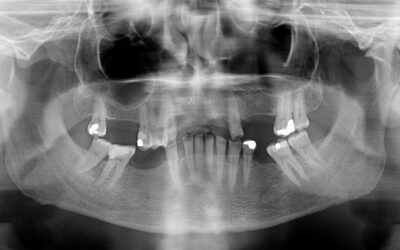

Keep Your Cool When a Filling or Crown is Lost Fillings and crowns never seem to get lost right before a dental visit, or in the morning on a day you have nothing planned, or even when you’re in town on a day when you can easily phone your dentist and come in for an...